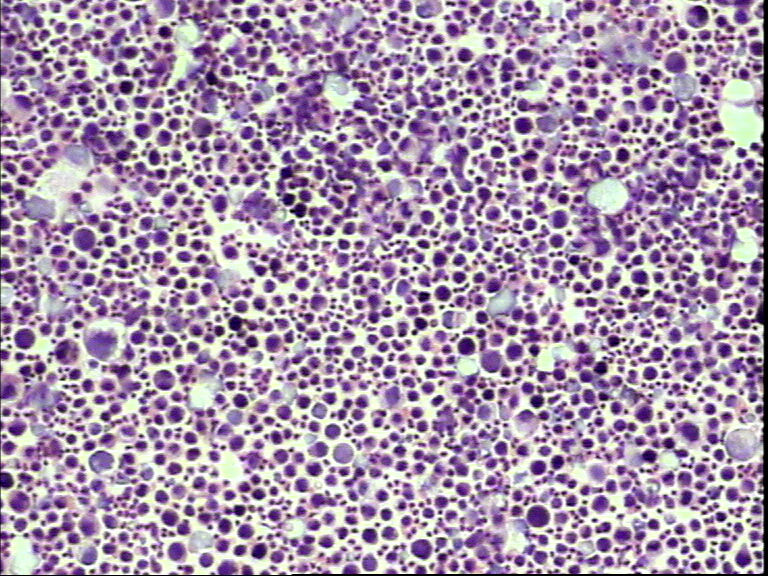

男性,80岁,腹水待查

• 男性,80岁,腹水待查图2

图2

间皮细胞

恶性细胞,需做IHC。

细胞有异型

低分化腺癌要重点考虑!

涂片中可见淋巴细胞、中性粒细胞及间皮细胞,个别核大深染的细胞是增生的间皮细胞,不是癌细胞,这种细胞很容易和癌细胞混淆,下诊断时一定要加小心。

细胞有异形,且胞浆内有空泡,需结合临床检查或做免疫组化已确诊。

考虑增生性间皮细胞

腺癌?,细胞形态暂时不讨论,做IC,会比讨论来的更实在。

可疑癌细胞,确实需要做IHC。